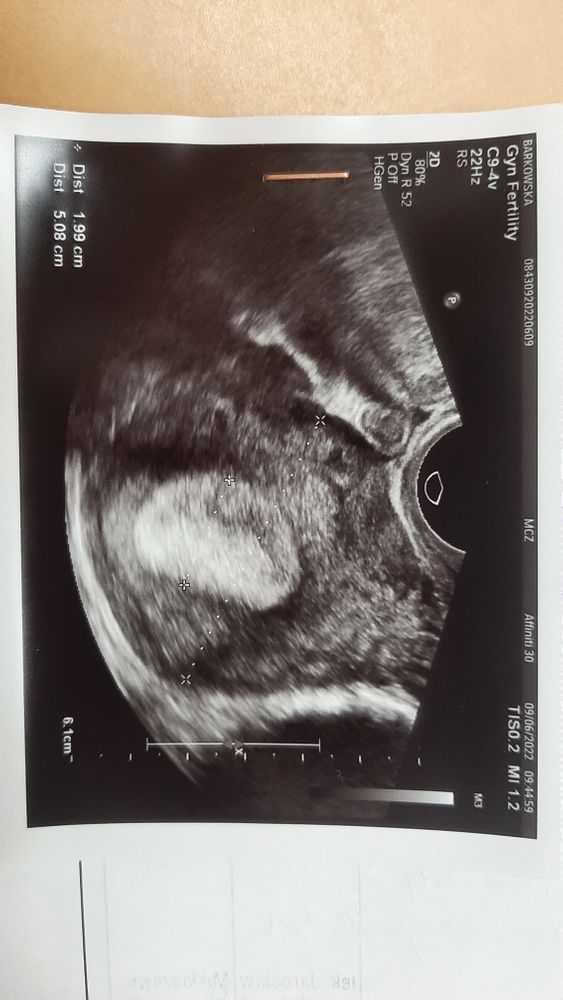

Изображение Это узи . Нет еще ПЯ. Оля Горбачёва,

Изображение Это у гинеколога показывает. Ещё нет ПЯ. Elena,

Изображение У гинеколога показывает. Нет еще ПЯ. Анастасия,